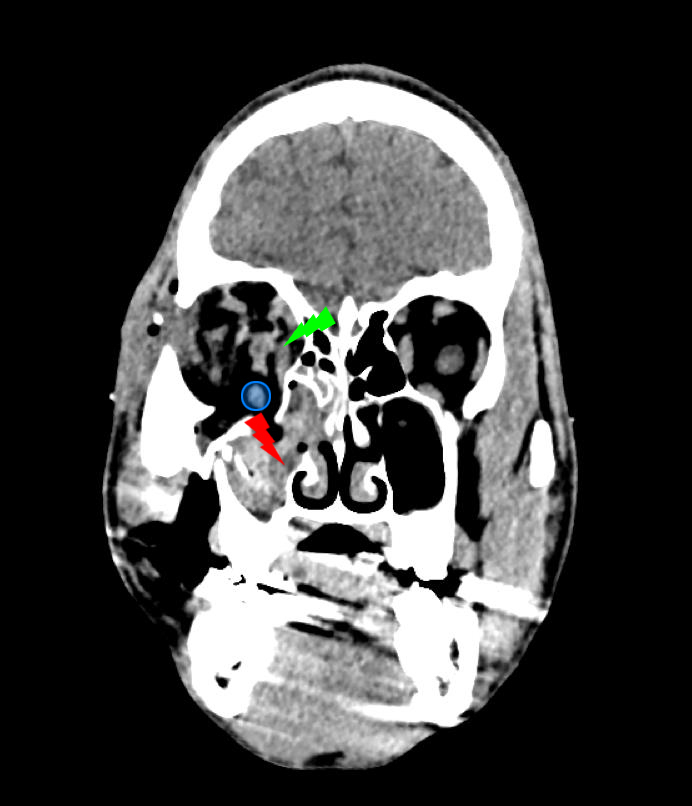

De garde, vous êtes appelé en salle de surveillance post-interventionnelle (SSPI) dans votre hôpital où vient d'être admis un patient conduit sur place par le service d'aide médicale d'urgence (Samu). Il s’agit d’un jeune homme de 20 ans, Monsieur D. Il aurait été victime, entre autres, d’un tir de Flash-Ball lors d’une rixe. Le projectile l’a atteint au niveau de la pommette et de l’orbite droites. Il présente une plaie de la région jugale haute, un œdème des paupières supérieure et inférieure. Vous ne visualisez pas le globe oculaire spontanément. Il est hémodynamiquement stable.

Traumatisme orbitaire = à risque de fracture des parois de l’orbite et donc d’incarcération d’un muscle oculomoteur.